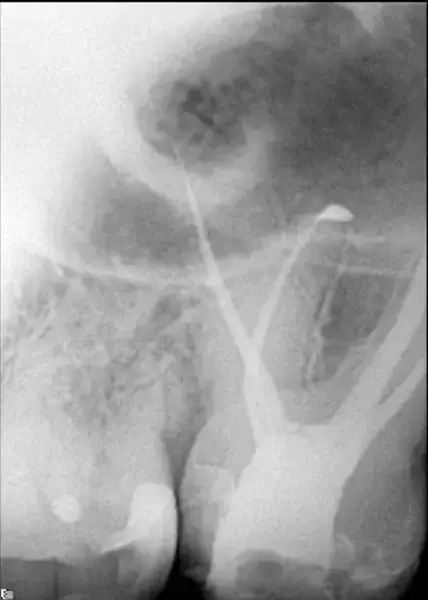

Третият случай подчертава способностите на изкуствения интелект, включен в DTX Studio Clinic, една от функциите на който е автоматичното проследяване на долночелюстния канал. В този случай се оказа много полезна функция. Пациентът е страдал от необратим пулпит на долен мъдрец. Той искаше да спаси зъба на всяка цена, тъй като не искаше да има имплант (моларният зъб е бил опорен зъб за мост). Рентгенографията сочи, че корените на молара се припокриват с канала на долната челюст (фиг. 12). Беше направен 3D скенер и върху него софтуерът проследи долночелюстния канал, който припокриваше молара в панорамния изглед. Ендодонтският режим показа, че каналът заобикаля букалната област, като леко докосва медиобукалния канал (фиг. 13–15). Рентгенографията, направена непосредствено след кореновото лечение, извършено през коронката, показа пълна обтурация на всички канали (фиг. 16)

Фиг. 12 Предоперативна рентгенография, показваща непосредствената близост между канала на долната челюст и мъдреца.